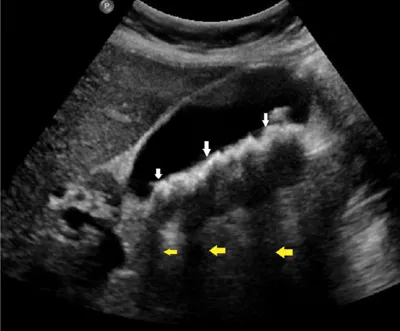

Your differential diagnosis already includes gallbladder pathology. Therefore, an ultrasound is the most important imaging test. The probe is placed over the ninth rib costal margin in the right mid-clavicular line. You see the image shown in Figure 1.

Figure 1.

Describe what you see and read on

The ultrasound shows a gallbladder in the sagittal view. Gallstones (white arrows) cast dark shadows (yellow arrows) on ultrasound. Changing the patientās position demonstrates the stones are mobile. This image does not show a thickened gallbladder wall, or a black rim around the gallbladder wall suggesting fluid (pericholecystic fluid). The patientās Murphyās sign was negative on physical examination.